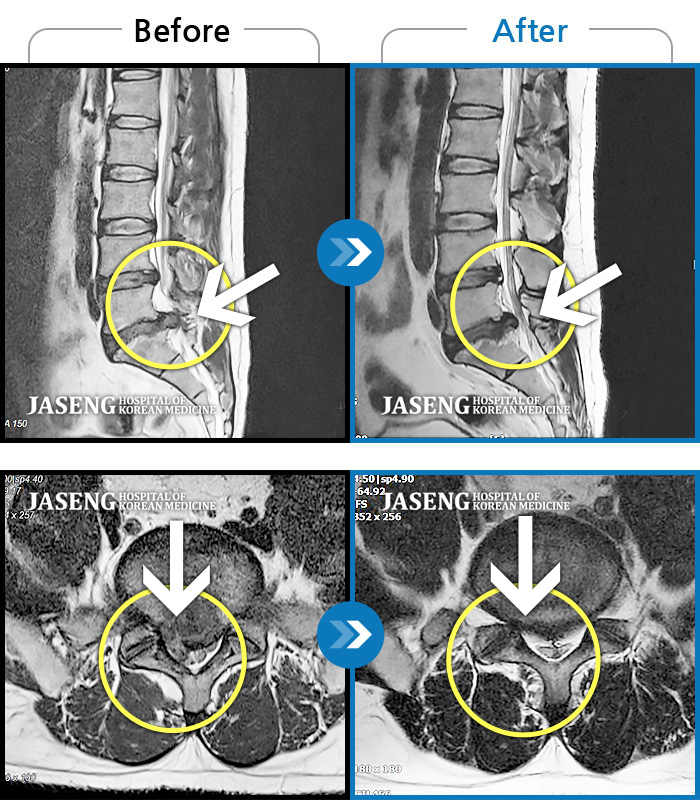

MRI 치료사례

디스크 파열 후 허리 골반 통증, 허리 숙일 때 다리 당김 증상